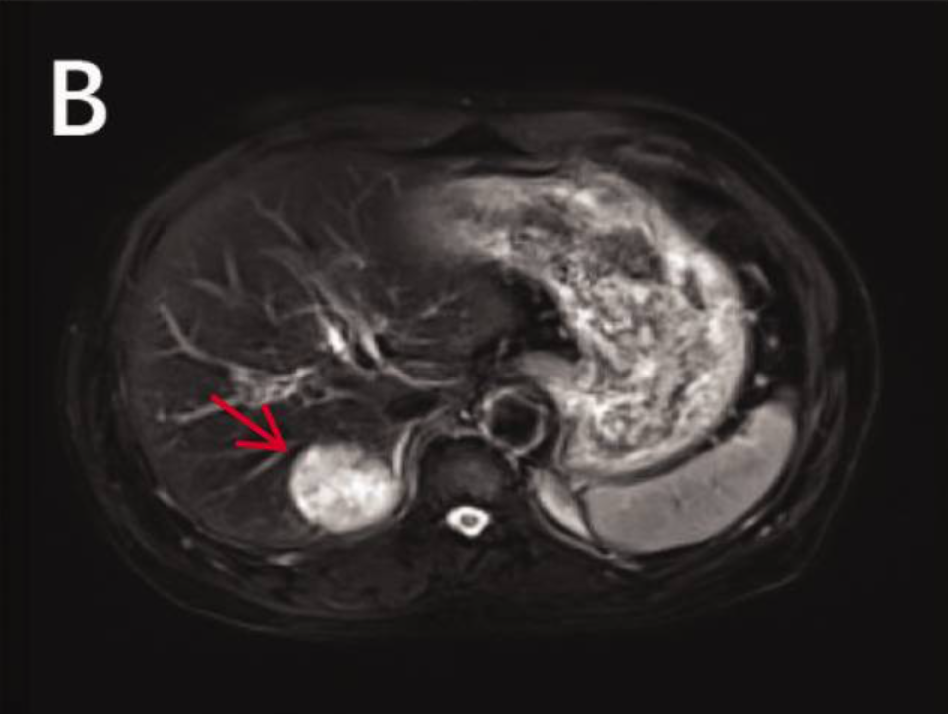

病史摘要:60余岁男性患者,有冠状动脉钙化和良性前列腺增生病史。2024年中期常规体检发现肝占位性病变,无腹痛、体重下降、呼吸功能障碍等症状。 诊疗过程:胸部CT发现右肺上叶孤立性毛刺状结节,腹部MRI提示肝病灶可能为肝细胞癌,PET-CT显示多处高代谢活性。肿瘤标志物CEA显著升高。行肝段切除术,病理提示肺来源转移性神经内分泌癌;后行右肺上叶部分切除术,确诊原发性肺大细胞神经内分泌癌伴脏